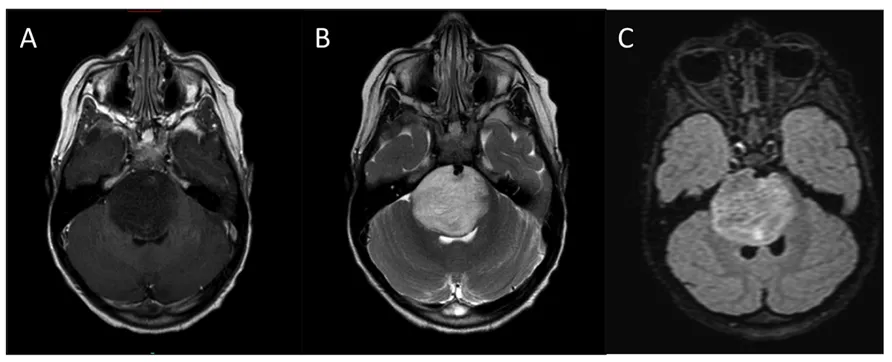

● 背侧外生性脑桥胶质瘤

背侧外生性脑桥胶质瘤起源于第四脑室底的室管膜下胶质细胞,通常向阻力最小的方向生长,进入脑室腔和蛛网膜下池。儿科患者通常表现为眼外肌功能障碍,这是由于桥旁网状结构受累所致。这些良性病变在磁共振成像上通常表现为相当大的肿块,有时可能类似于小脑星形细胞瘤。然而,与小脑星形细胞瘤不同的是,背侧外生性桥脑胶质瘤在阻塞第四脑室后,直到病程晚期才会产生脑积水。手术的目标应该是最大程度地切除肿瘤,同时最小化手术并发症。

为了更加安全、彻底地切除肿瘤,必须在术中持续使用对运动、感觉和脑神经功能的神经生理监测。

神经外科手术的另一个关键要点是不要超出第四脑室的预期解剖位置,以避免发生新的颅神经功能障碍并增加其他神经功能缺损的风险。神经外科手术切除后,可根据需要辅以化疗和放疗。

背侧外生性脑桥胶质瘤